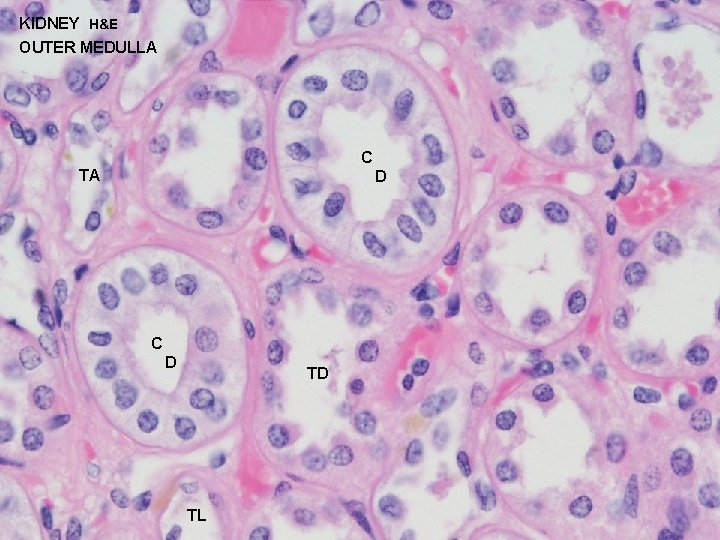

URINARY SYSTEM THE NEPHRON & COLLECTING DUCTS MEDULLA: OUTER ZONE 1 - STRAIGHT PORTIONS OF PROXIMAL TUBULE (THICK DESCENDING) 2 - STRAIGHT PORTIONS OF DISTAL TUBULE (THICK ASCENDING) 3 - THIN SEGMENTS OF LOOP OF HENLE (DESCENDING & 4 -ASCENDING) COLLECTING DUCTS INNER ZONE 1 - THIN SEGMENTS OF LOOP OF HENLE (DESCENDING & 2 -ASCENDING) COLLECTING DUCTS

URINARY SYSTEM THE NEPHRON & COLLECTING DUCTS MEDULLA: OUTER ZONE 1 - STRAIGHT PORTIONS OF PROXIMAL TUBULE (THICK DESCENDING) 2 - STRAIGHT PORTIONS OF DISTAL TUBULE (THICK ASCENDING) 3 - THIN SEGMENTS OF LOOP OF HENLE (DESCENDING & 4 -ASCENDING) COLLECTING DUCTS INNER ZONE 1 - THIN SEGMENTS OF LOOP OF HENLE (DESCENDING & 2 -ASCENDING) COLLECTING DUCTS

KIDNEY H&E OUTER MEDULLA C TA D C D TD TL